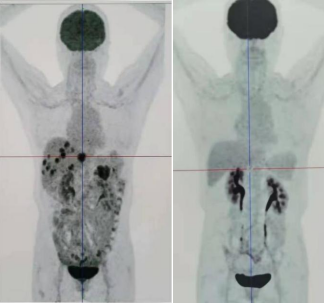

PET-CT(2020年11月vs2021年10月):肝脏20多个转移灶和原发病灶完全消失